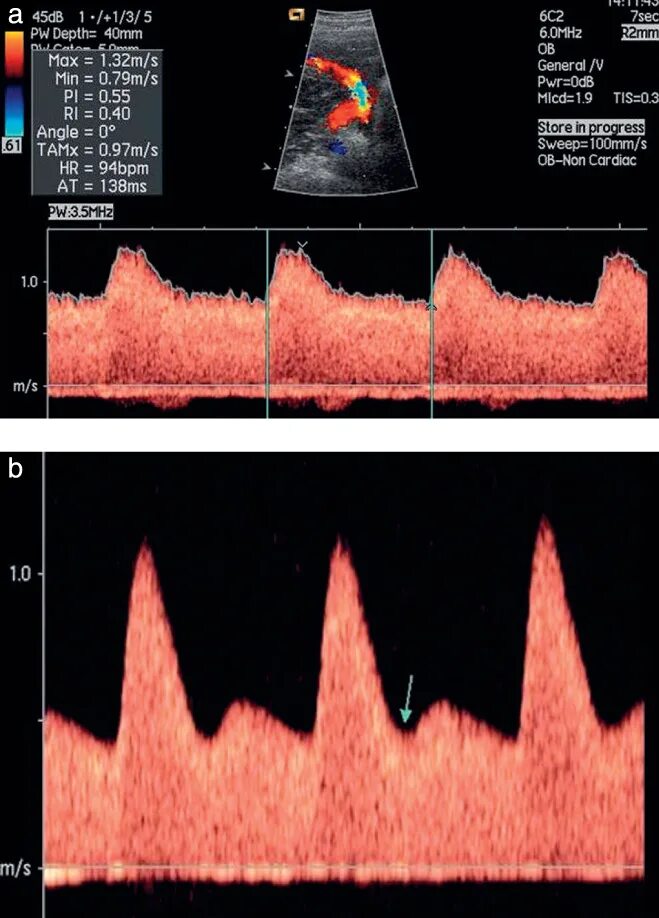

Допплерометрия маточных